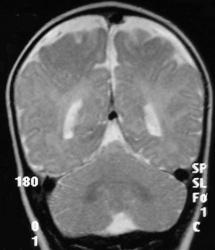

МРТ головного мозга

• Выраженное расширение субарахноидального пространства над лобными долями, обусловленное уменьшением объема лобных долей;

• Атрофия белого вещества;

• Изменение паттерна извилин: Имеются участки, где четко видны мелкие извилины, их количество увеличено по сравнению с нормальным. На других участках, напротив, извилины плоские, широкие;

• Граница между белым и серым веществом четко не дифференцируется;

• Сильвиева щель расширена, больше слева;

• Отчетливо выявляется зияние островка, что говорит о том, что височная доля не сформирована;

• Определяются зоны гиперинтенсивного сигнала в субинсулярных отделах;

• Желудочки расширены.

• Атрофия лобных долей;

• Смешанная гидроцефалия;

• Признаки нарушения формирования борозд лобных долей и перисильварного региона;

• Симметричная двусторонняя передняя перисильварная полимикрогирия;

• Атрофия (гипогенезия) мозолистого тела.